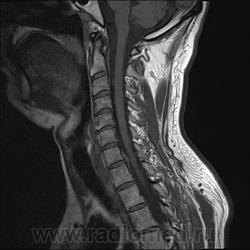

Грыжа диска. А где аксиалы?

Шейный остеохондроз.Грыжа С7-Th1.Не исключено наличие миелопатии на этом уровне, но боюсь ошибиться-изображения мелковаты ,идаже кажется, что есть повышение МРС от спинного мозга по Т1( скорее всего-артефакты?).

Левосторонняя парамедианная с компрессией корешка.

а это не перидурит??? смотрели месяц назад (в начале заболевания) было меньше.

Посмотрите на STIRе. Если жидкости нет, то простая грыжа. На этих сканах вообще-то жидкости не видно. За месяц грыжа могла и подрасти, смотря как лечили.

По-моему, только грыжа.